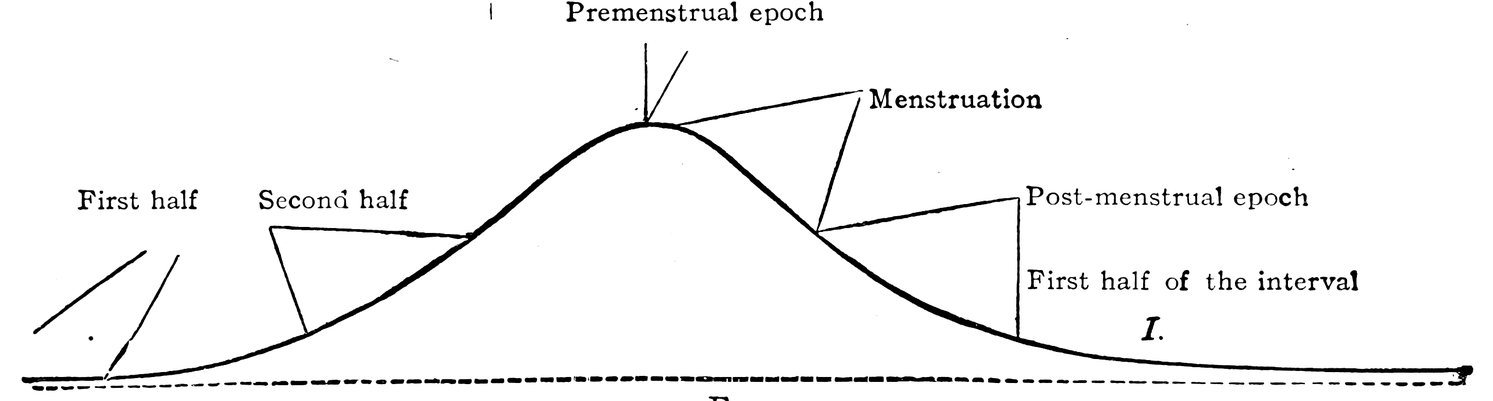

| 6. | Curve of rhythmical variations | 20 |

Of great interest are the facts which have, in recent times especially, been scientifically established, pointing to a certain periodicity, to an undulatory movement of the general bodily functions of the female organism, dependent upon the sexual life. The observations of Goodman, Jacobi, von Ott, Rabuteau, Reinl and Schichareff, have shown that in woman the principal vital processes pursue a cycle made up of stages of increased and diminished intensity, and that this periodicity of the chief general processes of vital activity finds expression also in the functions of the reproductive organs. Goodman has compared this play of general vital functions to an undulatory movement. According to this writer, a woman’s life is passed in stages, each of which corresponds in duration with a single menstrual cycle. Each of these stages exhibits two distinct halves, in which the vital processes are respectively ebbing and flowing: in the latter we see an increase of all vital processes, a larger heat production, a rise in blood-pressure, and an increased excretion of urea; in the former we see, on the contrary, that all these vital processes display a diminished intensity. The moment when the period of increased vital activity is at an end, the moment when the ebb begins, corresponds, according to Goodman, to the commencement of the catamenial discharge.

Goodman sought for verification of this undulatory theory of the sexual life of woman in certain data regarding the bodily temperature and the blood-pressure. A more extensive research was undertaken by Jacobi, who, as the result of her observations, came to the following conclusions. In eight cases she noticed in the premenstrual epoch a rise of temperature ranging from 0.05° C. to 0.44° C. (0.09° F.–0.79° F.); and during the catamenial discharge a gradual fall of 0.039° C.–0.25° C. (0.072° F.–0.45° F.), never less, that is to say, than a quarter of a degree Centigrade; but in the majority of cases the temperature did not, while the catamenia lasted, regain the normal mean. She further observed in the generality of cases an increased excretion of urea during the premenstrual epoch; and a notable fall in blood-pressure during menstruation.

Reinl’s observations on healthy women, in whom menstruation ran a normal course, showed that in the great majority of cases in 19the premenstrual epoch the temperature was elevated as compared with that of the interval, that in eleven out of twelve cases the temperature gradually declined during menstruation, to fall in three-fourths of the cases below the mean temperature of the entire interval, and exhibiting in the post-menstrual epoch a still further depression, giving place, however, to a somewhat higher mean temperature during the first half of the interval. In the second half of the interval a higher mean temperature was observed than in the first half.

If we make a graphic representation of the mean differences in temperature commonly observed throughout the various stages of an entire menstrual cycle, we see that the curve does in fact take the form of a wave. That drawn by Reinl is shown in the following figure: (Fig. 5.)

Fig. 5.

The rising portion of the wave, the beginning of the tidal flow, corresponds to the second half of the interval; the height of the tidal flow, the crest of the wave, corresponds to the premenstrual epoch. As the flow gives place to the ebb, as the wave begins to decline, we come to the actual period of the catamenial discharge; later in the ebb is the post-menstrual epoch, and the lowest portion of the declining wave corresponds to the first half of the interval. Rhythmic changes corresponding to those observed in the temperature have been recorded—at least in isolated stages of the menstrual cycle—affecting the blood-pressure by Jacobi and by von Ott, affecting the excretion of urea by Jacobi and by Rabuteau, and affecting the pulse by Hennig. It is evident that the vital activity of the organism attains its maximum shortly before menstruation; and that with or immediately before the appearance of the catamenial discharge, a decline of that activity commences.